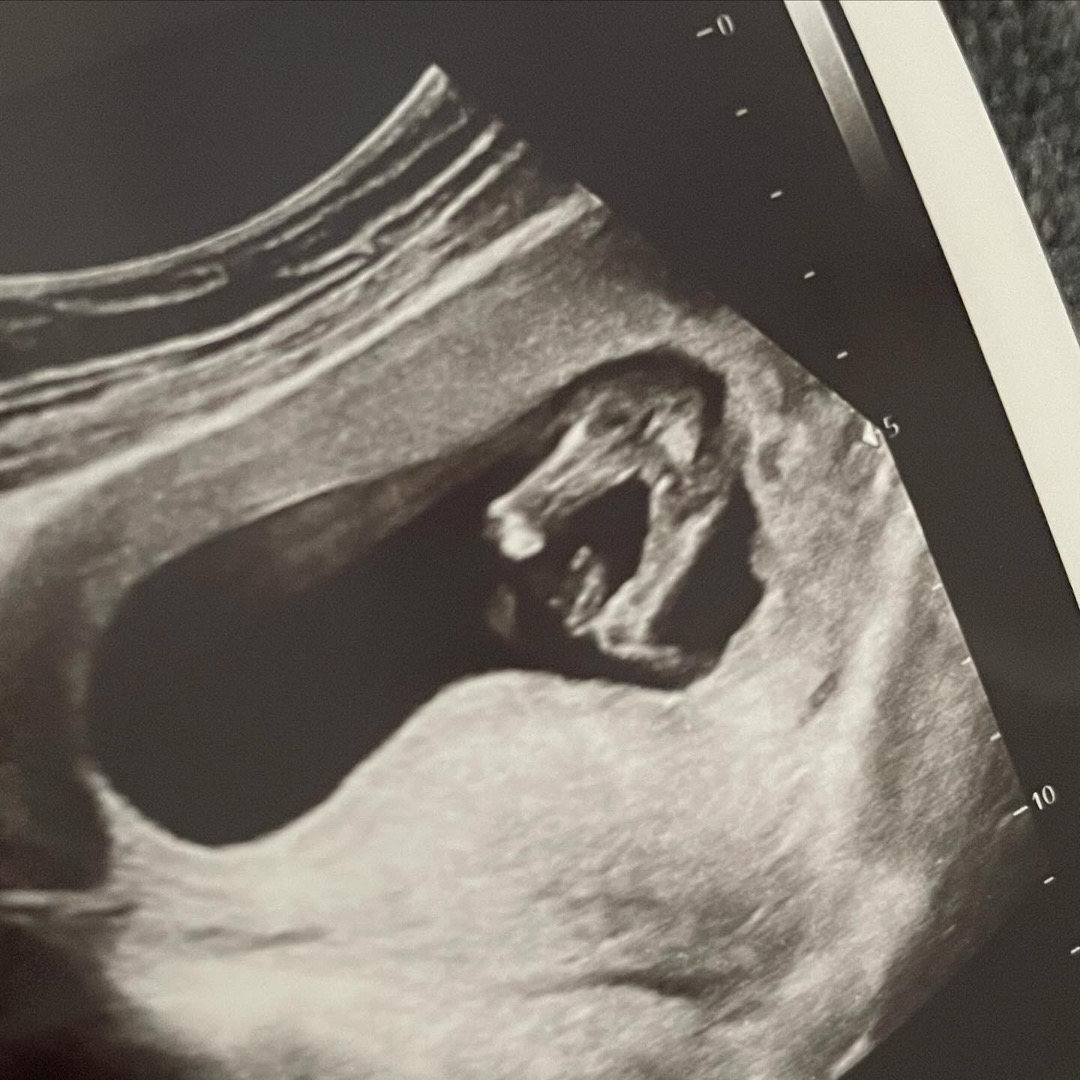

14주 다리사이

딸이라고 하셨는데 반전이 있을까용? 약간 투ㅏ어나온 부분이 신경 쓰여서용 참견 부탁두려용 ㅎㅎ

깨끗한데요 ~ 딸 같아요 ^^

여자도 성기가 안튀어나온게 아니라서 딸랑구 맞을듯 해요 ㅎㅎ 아들은 이시기에 애매하지 않은 로켓이더라구요!

14주 애매한 로켓이었는데 서브 병원에서도 딸같다했는데 16주 아들 확정됐슴다ㅋㅋㅋㅋㅋㅋㅋㅋㅋㅋㅋㅋㅋ